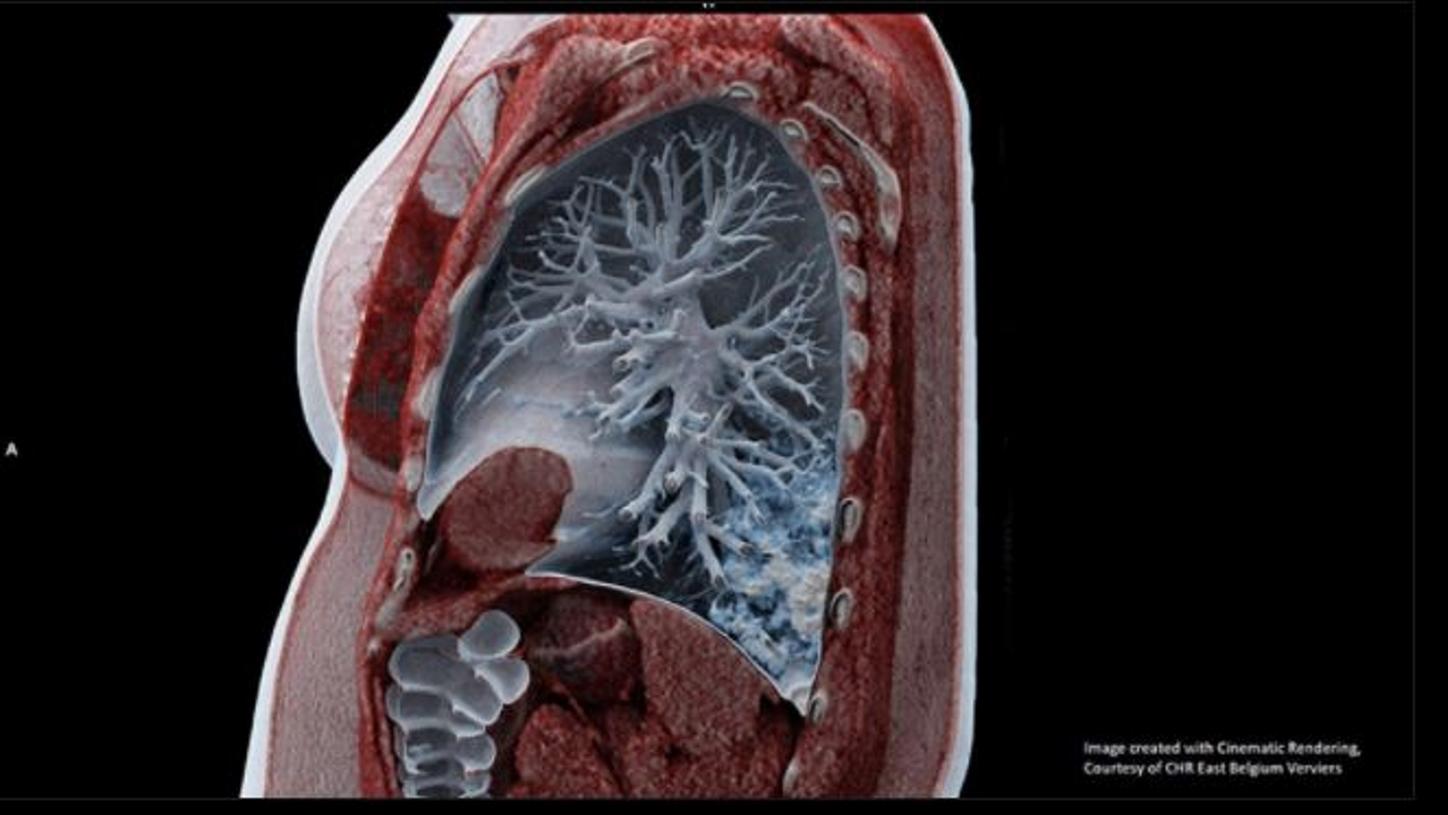

3 Image created with Cinematic Rendering, Courtesy of CHR East Belgium Verviers

- The development of the prototype algorithm and its deployment was a Siemens Healthineers collaborative effort, bringing together frontline healthcare providers, scientists and engineers from Princeton, clinical experts and developers from India, product development teams from CT, Digital Health and Syngo from Germany. The Pulmonary Density feature is new in VA12A without FDA Clearance. According to FDA policy “Enforcement Policy for Imaging Systems During the Coronavirus Disease 2019 (COVID-19) Public Health Emergency issued in April 2020, the manufacturer is allowed to market this feature without FDA-clearance. This policy is intended to remain in effect only for the duration of the public health emergency related to COVID-19 declared by the HHS Secretary in accordance with section 319(a)(2) of the Public Health Services Act (42 U.S.C. 247d(a)(2)). Pulmonary Density results are not indicated for the diagnosis of COVID-19. Only in vitro diagnostic testing is currently the definitive method to diagnose COVID-19.